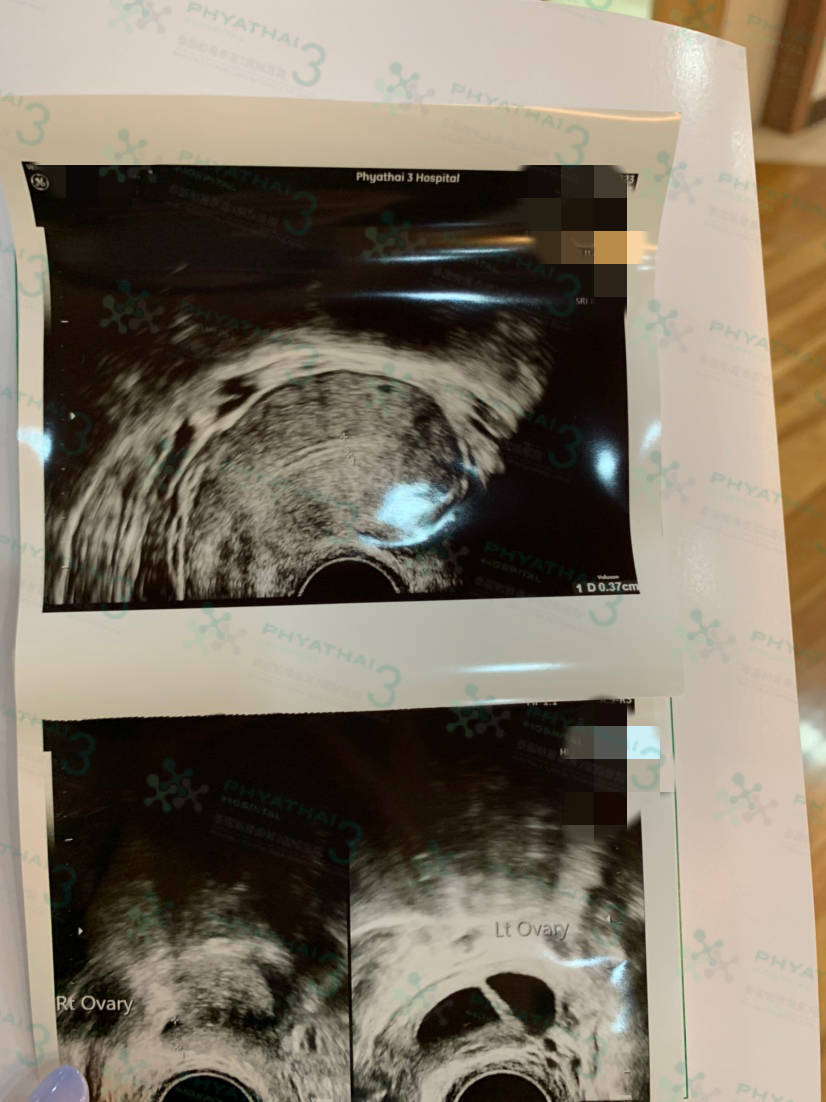

:提前顺利的带小王子回国啦 女士验孕成功,血值翻倍。今天女士孕期6周,按照医生预约来监测平躺着床情况。当阴超...